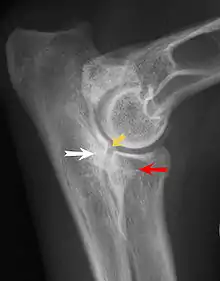

Most primary lesions are related to osteochondrosis, a disease of the joint cartilage, and osteochondritis dissecans (OCD), the separation of a flap of cartilage on the joint surface. Other common causes of elbow dysplasia include an ununited anconeal process (UAP) and fragmented or ununited medial coronoid process (FCP or FMCP).[1]

In OCD, the normal change of cartilage to bone in the development of the joint fails or is delayed. The cartilage continues to grow and may split or become necrotic. The cause is uncertain, but possibly includes genetics, trauma, and nutrition (including excessive calcium and decreased vitamin C intake).[4] OCD lesions found in the elbow at the medial epicondyle of the humerus are caused by disturbed endochondral fusion of the epiphysis of the medial epicondyle with the distal end of the humerus, which may in turn be caused by avulsion of the epiphysis.[5] Specific conditions related to OCD include fragmentation of the medial coronoid process of the ulna (FMCP) and an ununited anconeal process of the ulna (UAP). All types of OCD of the elbow are most typically found in large breed dogs, with symptoms starting between the ages of 4 and 8 months.[4] Males are affected twice as often as females. The disease often affects both elbows (30 to 70 percent of the time), and symptoms include intermittent lameness, joint swelling, and external rotation and abduction of the paw.[6] Osteoarthritis will develop later in most cases.

UAP is caused by a separation from the ulna of the ossification center of the anconeal process.[7] FMCP is caused by a failure of the coronoid process to unite with the ulna.

Diagnosis is through x-rays, arthroscopy or CT (computed tomography). In cases with significant lameness, surgery is the best option, especially with UAP. However, conservative treatment is often enough for cases of FMCP and OCD of the medial humeral epicondyle. The dogs are exercised regularly and given pain medication, and between the ages of 12 and 18 months the lameness will often improve or disappear.[4] Control of body weight is important in all cases of elbow dysplasia, and prevention of quick growth spurts in puppies may help to prevent the disease.